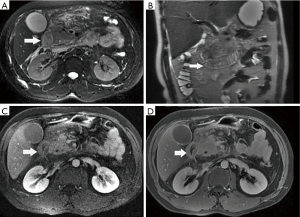

Among the AP patients, wall thickening involved duodenum (Figure 1) (27%), ascending colon (26%), stomach (20%), transverse colon (15%), jejunum (Figure 2) (14%) and ileum (6%). Dilatation of the gastrointestinal tract was seen in 8% (Figure 2, Table 2).

In this study gastrointestinal tract wall thickening was the most common finding in AP patients. Inflammatory substances can stimulate the gastrointestinal tract in patients with AP, leading to the excessive output of gastric juices and subsequent mucosal and submucosal edema (27). Some patients exhibit a three-layer structure referred to as the “target sign” (28). Tolan et al. (29) considered this pattern acute wall edema, and noted a direct correlation with inflammatory activity. In this study we found most AP patients exhibited gastrointestinal tract wall thickening, some with a stratified appearance on MRI that was similar to the “target sign” (28). After treatment, the mural stratification resolved on follow-up MRI. Our results suggested that the thickened intestinal wall in AP patients is derived from acute wall edema and can resolve soon after treatment.